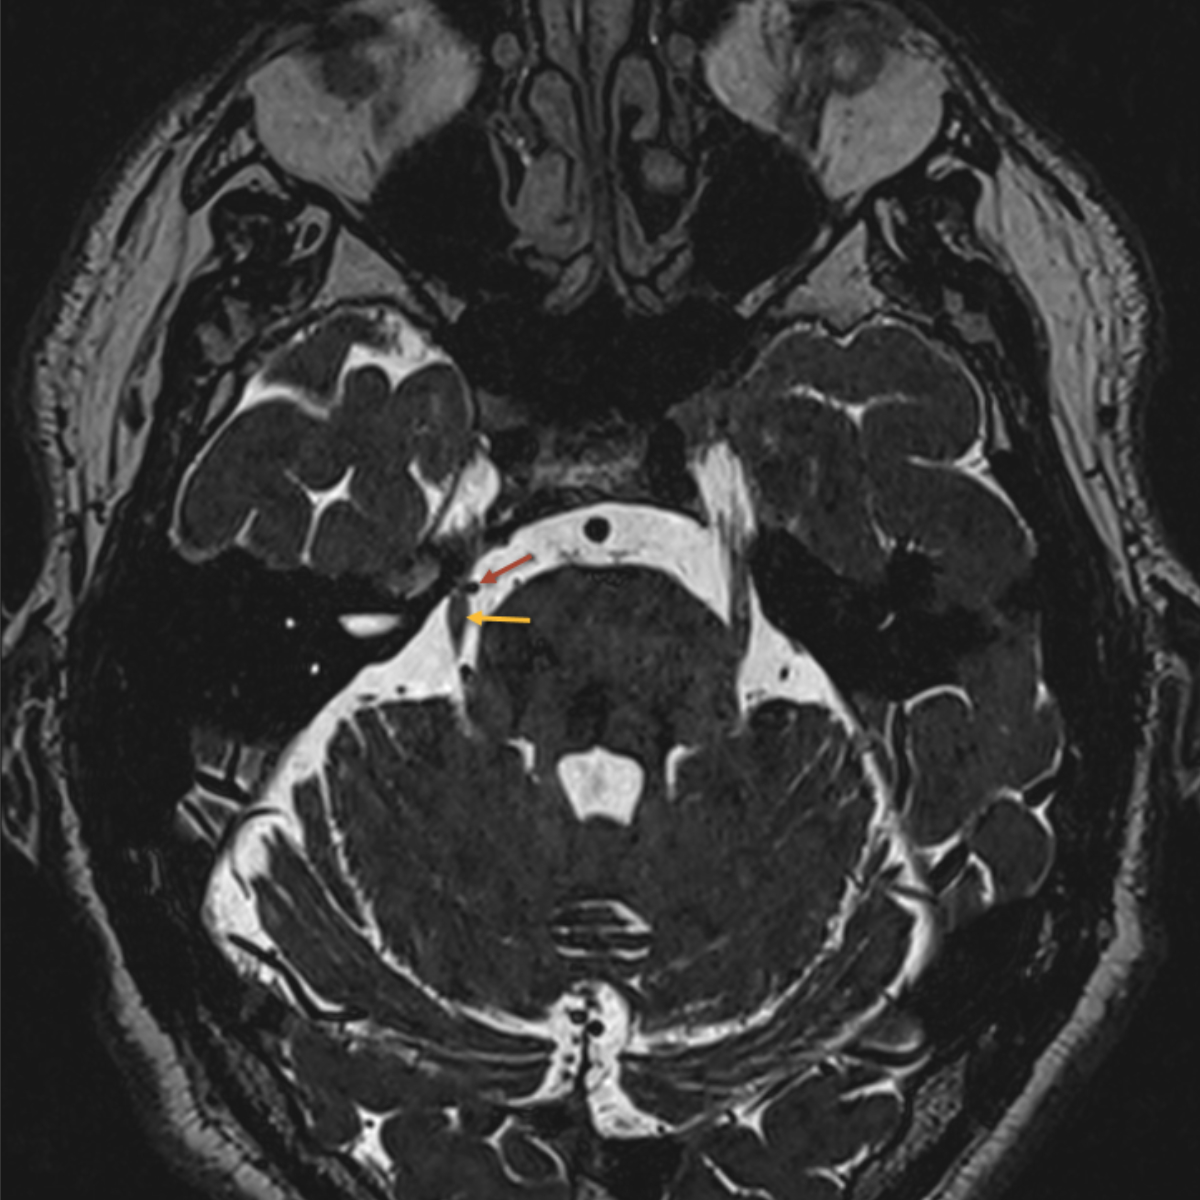

Every patient with suspected trigeminal neuralgia requires imaging to distinguish between classic trigeminal neuralgia and secondary causes. The current gold standard is magnetic resonance imaging (MRI), including high-resolution constructive interference in steady-state (CISS) sequences to exclude neurovascular compression, T2 sequences to detect possible inflammatory processes and angiography [9, 10] (figures 2, 3, 4). When assessing a possible pathological neurovascular contact, it is important (for planning potential surgical procedures) to distinguish between nerve displacement and atrophy [12].

Figure 3MRI showing pathological neurovascular contact between the right superior cerebellar artery (red arrow) and the trigeminal nerve (yellow arrow).